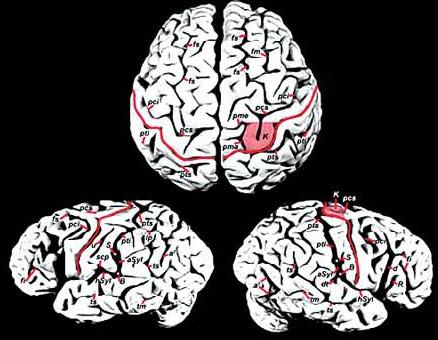

最近,从医学专业杂志《刺针》上传来一则好消息:麻省理工学院著名认知科学家斯帕克初步认定:爱因斯坦的大脑结构与其特殊功能之间存在某种内在联系。斯帕克发现,就在位于齐耳高度、从脑前延伸至后部2/3的下顶叶处,即人脑处理数学思维、三维形象和空间关系等的关键部位,“爱脑”确实与“凡脑”不同:后者的顶叶和颞叶之间通常由“西尔维裂沟”所分裂,形成一道脑上天堑;而“爱脑”的裂纹却在接近顶叶处戛然而止,并急转直上,绕过顶叶不再分裂。于是“天堑变通途”,保持了顶叶的相对完整,而且顶盖骨也模糊不见,因此整个大脑顶叶沟壑纵横,路径曲折,密密麻麻覆盖全脑,联结面积比普通人大约15%。这意味着,更多的脑细胞或神经元更易于联系,可以更好地协调工作。

随后,斯帕克又在《纽约时报》上发表专文,阐明大脑顶叶即每一大脑半球顶端的后部象限,位于初始视觉和体感之间的地方,是空间感的区域。而这也正是爱因斯坦借助“顶叶智力”确定各类事物的部位,从而在下侧小叶或骨叶低处隆起专司抽象数学和空间推理的超凡直觉与优异数值演算能力的区域。

关于爱因斯坦大脑“下叶区智慧”的研究也有新的发现。不久前,由加拿大麦克马斯特大学教授桑德拉,威尔特森领导的研究小组发现,位于爱因斯坦后脑左右半球的上部顶下叶区域比常人大15%,其机理非常发达。这项研究成果发表在著名医学杂志《柳叶刀》上,认为爱因斯坦的天才是天生的,并非全靠后天用功求学得来,证实后天的努力虽然也能成才,但天生天才也是事实。大脑中负责视觉思考和空间推理的顶下叶区域发达,对一个人的数学思维、想象力以及视觉空间认识都发挥着重要作用。这一研究解释了为何爱因斯坦有独特的抽象思维与过人的空间认知能力——左右半球的上部顶下叶区域比常人要大。

斯帕克指出,爱因斯坦大脑左右上部顶下叶区一般大,二者都大于常人15%,而脑重不增。有了这个完整、宽大的小叶,即可通过千百万突触所构成的微循环,容纳更丰富也更紧凑的空间与数学推理的逻辑思维线路。因此,思维敏捷、思路活跃的爱因斯坦之所以成为绝世天才,很可能是胎儿发育早期自然形成的。

特异之二:爱因斯坦大脑不仅在左右上部顶下叶区比一般人大15%,更不寻常的是顶下小叶区缺少常人都有的一条特殊的裂缝,导致两块关键的脑部区域成为一个整体。有了这个完整、宽大的小叶,即可通过千百万突触所构成的微循环,容纳更丰富也更紧凑的空间与数学推理的超凡逻辑思维缨路。

特异之四:一般人的大脑里有一条叫做“外侧裂”的脑沟穿过这里,沟的尾稍嵌入一块名为“缘上回”的区域。而在爱因斯坦的大脑照片上则显示,他的“外侧裂”在进入顶叶下部区域之前就与另一条脑沟合并,“缘上回”也显得更为完整。维特森认为,一般情况下,大脑中神经连接密集的地方形成凸起的脑回,而神经连接比较稀少的地方则凹下变成脑沟。爱因斯坦戛然而止的外侧沟,正好说明他的顶叶下部区域比一般人的神经连接更密集。

特异之五:这是迪安·法尔克在《进化神经科学前沿》上发表的最新研究成果。爱因斯坦大脑表层的很多部分没有凹沟,因此神经细胞可以通行无阻地沟通,思维也能够活跃无比。维特森指出,爱因斯坦大脑的顶叶异常发达,在形态上也有特异之处,例如侧脑裂并不明显,特别是左半球。因此顶叶下段皮质中的神经元易于相互联系,使爱因斯坦在视觉、空间认知、数学思考、运动知觉这些认知领域中,表现出超卓的智力。

特异之六:法尔克还发现,爱因斯坦大脑两侧顶叶区域的凹槽和凸起模式十分罕见。她由此推测,这在一定程度上可能同爱因斯坦善于把物理问题概念化的卓越才能有关。她指出,爱因斯坦作为“综合性思想家”的才能可能源于他大脑顶叶不同寻常的结构。这项研究成果刊登在最新一期的《进化神经科学》杂志上。